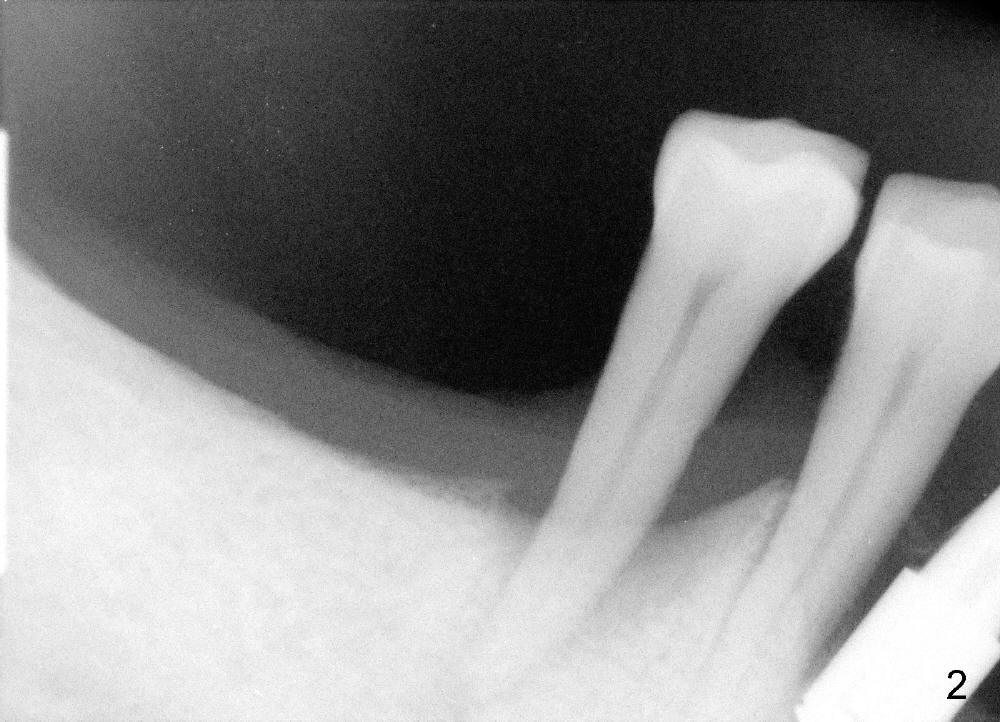

To avoid paresthesia on the right side, several preop PAs are taken (Fig.1-4) so that we know how to take good X-ray for this gagging patient.  At first, #2 Sensor is used to take the first PA (Fig.1).  It does not show the apex of the tooth #29.  The second PA is a little better (Fig.2), but the mental nerve is out of view.  Then #1 sensor is used.  It allows us to position the sensor lower (Fig.3), but the image is blurred.  When it is retaken, the image is clear (Fig.4), showing the proximity of the mental nerve loop (Fig.4': red dashed line) to the root tip of the tooth #29 (R).